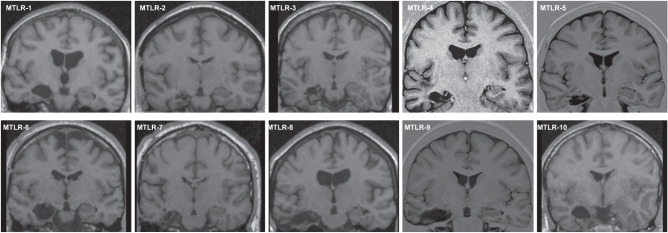

In total, thirty-four participants took part in the experiment and thirty participants were included in the final dataset of our study (18 female, 12 male; Table 1). Eleven patients were recruited through our Department of Neurology who had undergone unilateral partial resection of the right medial temporal lobe (MTLR), including the hippocampus, due to hippocampal sclerosis and intractable epilepsy (n = 7) or due to removal of a benign tumor (n = 4) (Fig. 5, Table 2). The other inclusion criteria for patients were as follows: Age 18–65 years, fluent German (at least C1 level), postoperative neurological examination was normal, no other neuropsychiatric or severe internal diseases were reported, vision and hearing were normal or corrected to normal, no subjective memory complaints and navigation deficits in daily life were reported, and patients could be fully reintegrated into their personal and professional lives after surgery. Another requirement for inclusion in the study was a postoperative period of at least 6 months before the test to ensure sufficient recovery time after surgery. Each patient was matched with two healthy control participants in terms of gender, age, and education level. The control subjects were recruited via online advertising. Participants in the final data set were aged between 22 and 61 years, and four patients were taking anticonvulsant medication at the time of the study. Clinical cognitive assessment was not considered in the recruitment of patients, as patients with unilateral lesions are more likely to have subtle memory deficits that are not usually detected in routine examinations71. One patient and three control participants were later excluded due to cyber sickness or an additional neuropsychiatric disorder that was not known at the time of the experiment. All participants provided written informed consent in accordance with the Declaration of Helsinki and all procedures were approved by the local ethics committee of Charité-Universitätsmedizin Berlin. All ethical regulations relevant to human research participants were followed.

Fig. 5. Example images of unilateral lesions of the medial temporal lobe.

Postoperative coronal T1 MRI images of the brain show the unilateral lesion of the medial temporal lobe including the right-sided hippocampus, while the left-sided hippocampus is intact.

Lesion evaluation

All patients except No. 5 and No. 9 participated in previous studies where lesion size was analyzed72,73. Nos. 5th and 9th lesions were additionally analyzed using MRI scans from clinical routine. Briefly, 47 coronal T1 sections of the whole brain with an individual thickness of 4 mm were used to determine individual lesion size. The extent of each lesion was determined from rostral to caudal using previously proposed landmarks74–77.